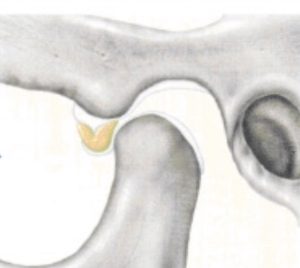

大きな口が開けられなくなる仕組み

関節円板がさらに強く変形している

口を開けると、下顎頭が変形した関節円板に引っかかる

関節円板の変形が強いので、引っ掛かりが外れない。そのため下顎頭が前に出られず、口が大きく開けられない。